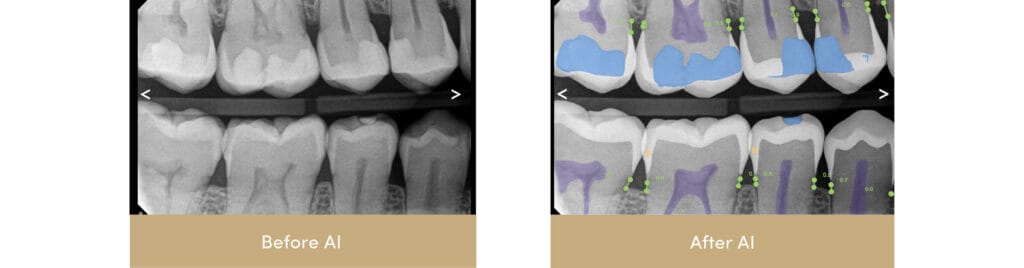

Dentists at the forefront of patient care use AI tools to analyze 2D X-rays. AI X-Ray analysis tools overlay digital X-Rays to detect decay that may not be visible to the human eye and share these findings with patients in real time. Because AI can see more contrast than the human eye, these tools help dentists identify changes in oral health that are otherwise difficult to detect, enabling them to treat problems before they progress. AI tools do not replace a dentist’s expertise; they enhance their visibility and precision.